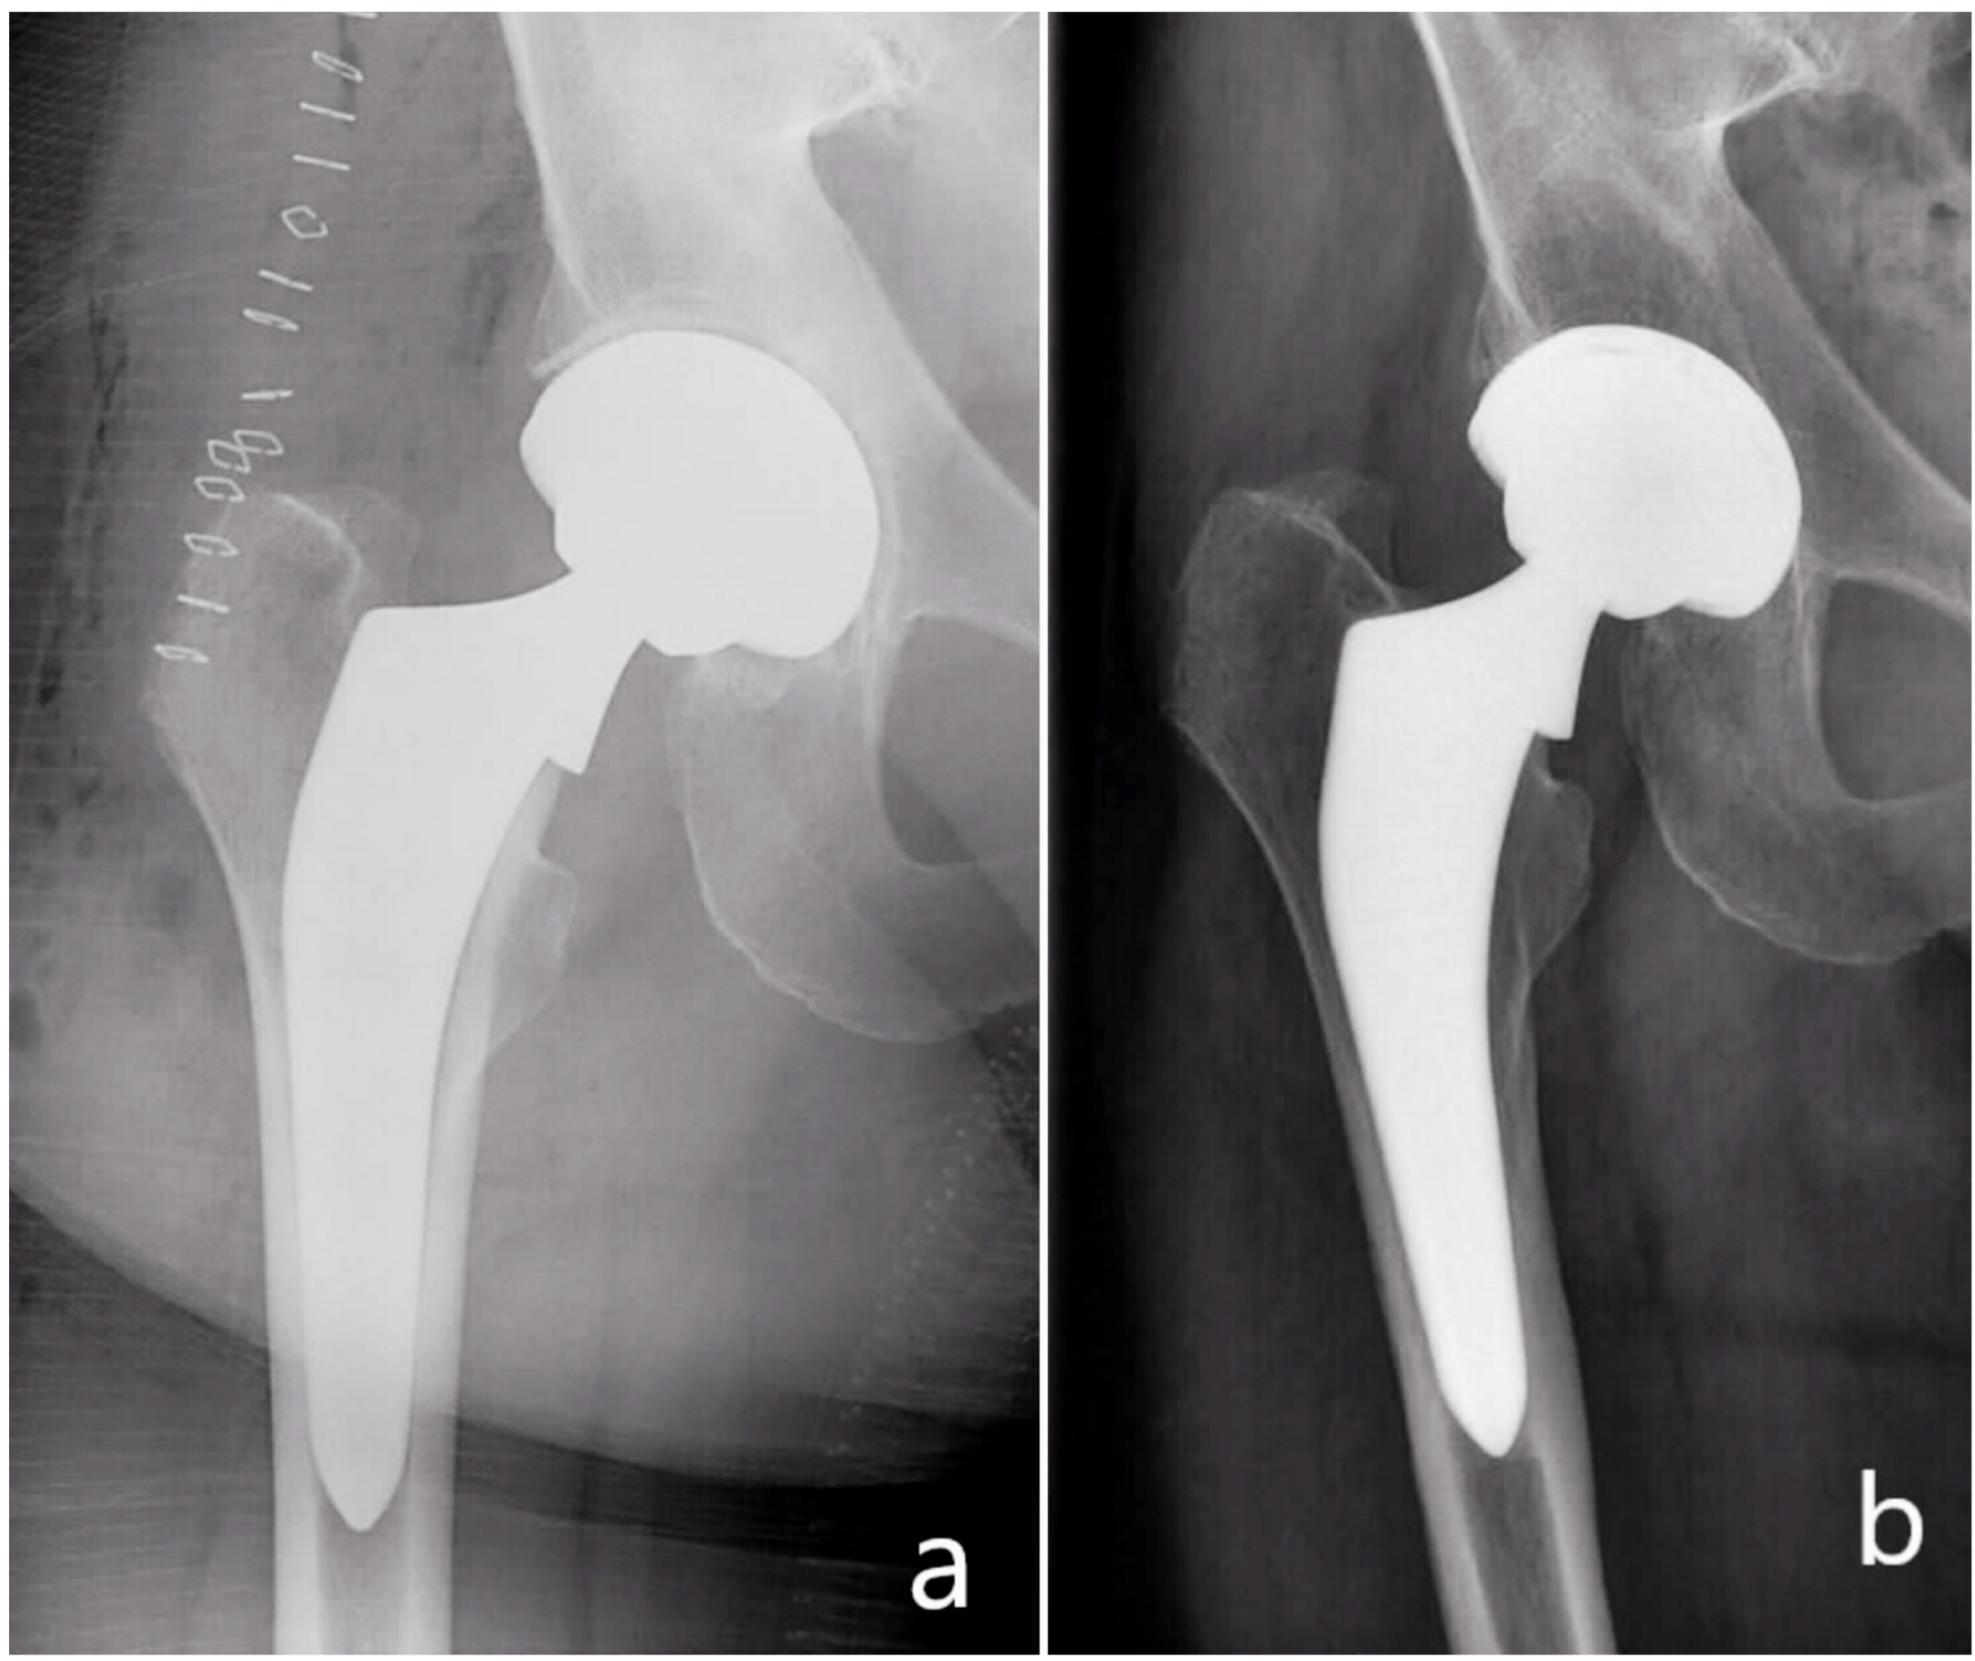

The subsidence frequency in this study was in total 4.2% (5 patients): 3.3% (4 patients) <5 mm and 0.8% (1 patient) >5 mm (Figure 5). The body mass index of these patients ranged from 26.4 to 27.2 kg/m2. In the postoperative radiographs, all five stems showed a neutral stem alignment and a collar to medial corticalis distance of <1 mm. The femoral neck-shaft angle in all five patients was in the normal range and varied from 129 to 134°. No fractures were detected. On the other hand, four of these five patients presented with a Dorr type B femur and one patient with a Dorr type C femur. Four of them were females. The mean age of the five patients was also 75 years higher than the total mean age of the whole collective (67.7 years). These factors, including poor bone quality, age, and femur geometry may have had a possible effect on the observed subsidence [40,41,42].

Figure 5.

(a) Postoperative radiograph, (b) radiograph of the same patient at three months showing subsidence of the stem.

Further analysis of the illustrated case in Figure 5 shows that the subsidence occurred although the collar abuts the resection plane of the femoral neck. An explanation of the subsidence occurrence here is a possible preexisting fracture or a missed intraoperative fracture. This theory is supported by the altered cortical bone distal to the lesser trochanter. In addition, the cortical thickening medial to the tip of the stem may be a consequence of a distal force transmission, which may, in turn, suggest a non-functional collar.